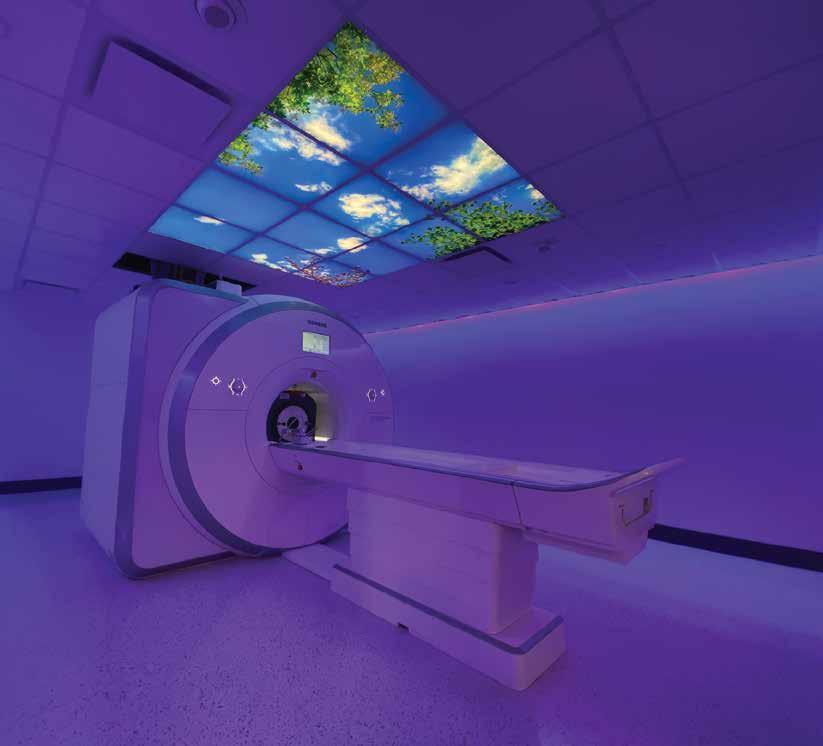

Calgary is already a recognized hub for cancer research, treatment and care. That’s nothing compared to what we’re poised to become when the doors to the new Calgary Cancer Centre - one of the largest comprehensive cancer centres in North America - open in 2024. But big dreams need big support. Help us raise $250 million to accelerate research innovations and provide world-leading cancer care and treatment right here in Calgary.